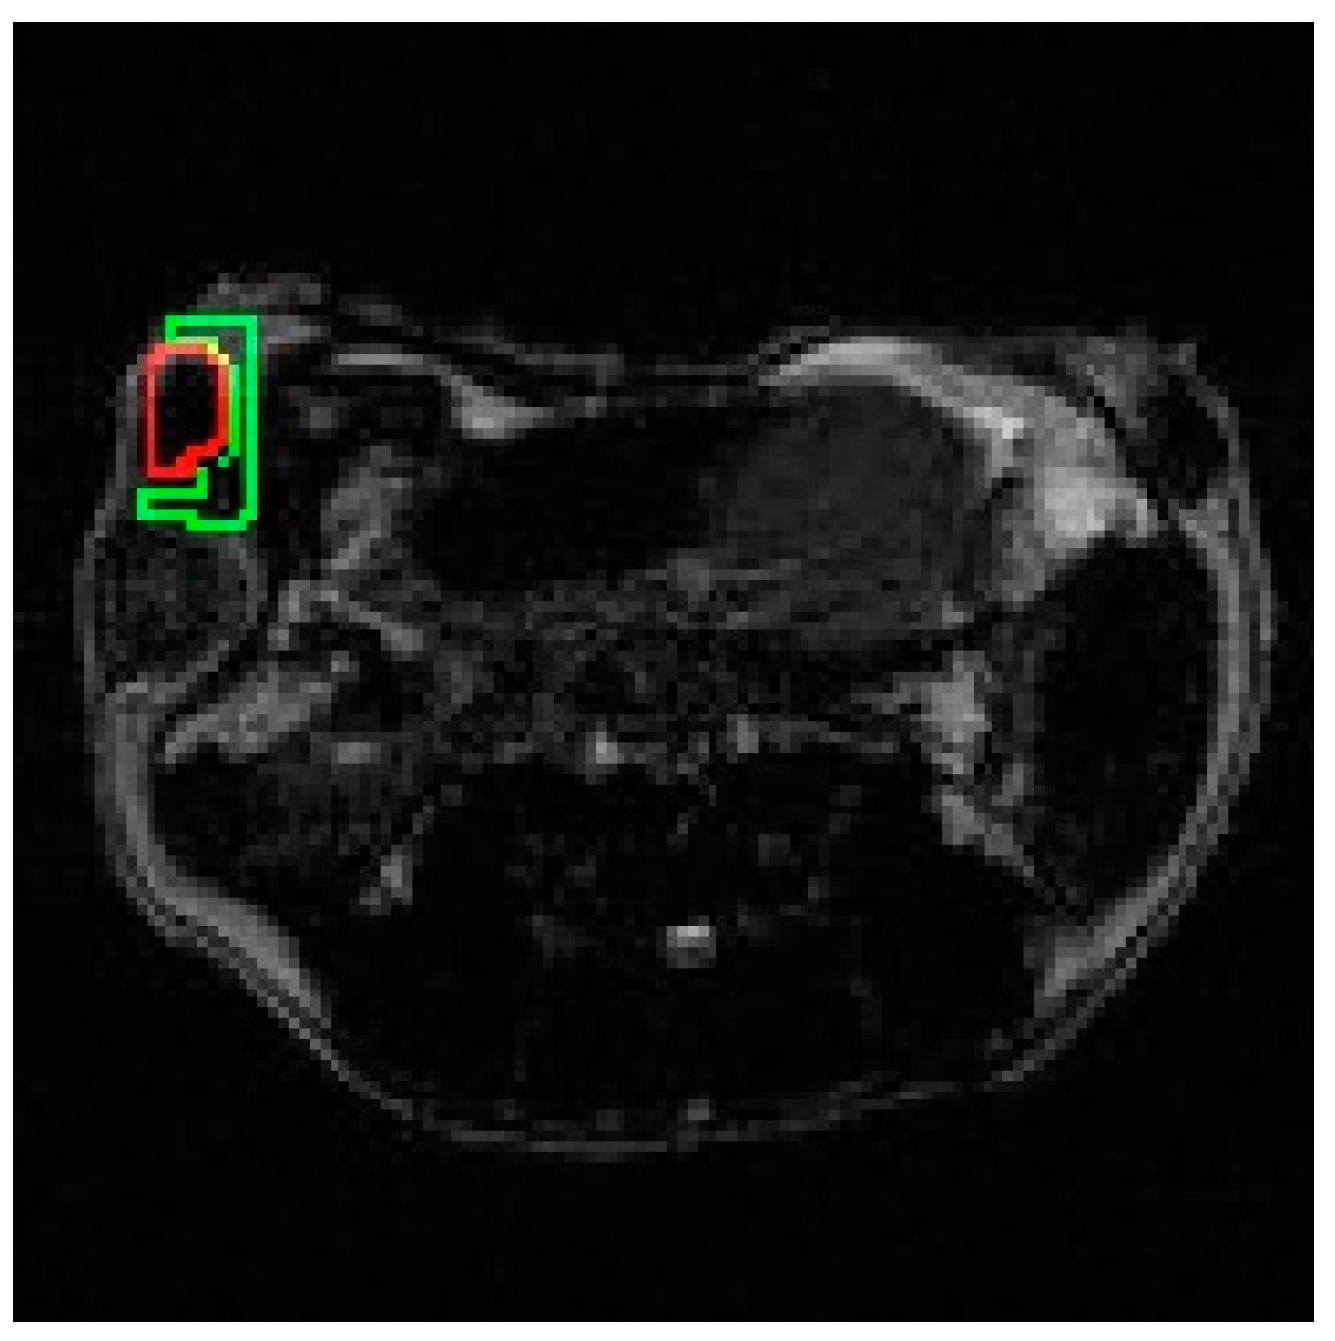

2.6. Selection of ROIs

3.2. In Vivo Experiments